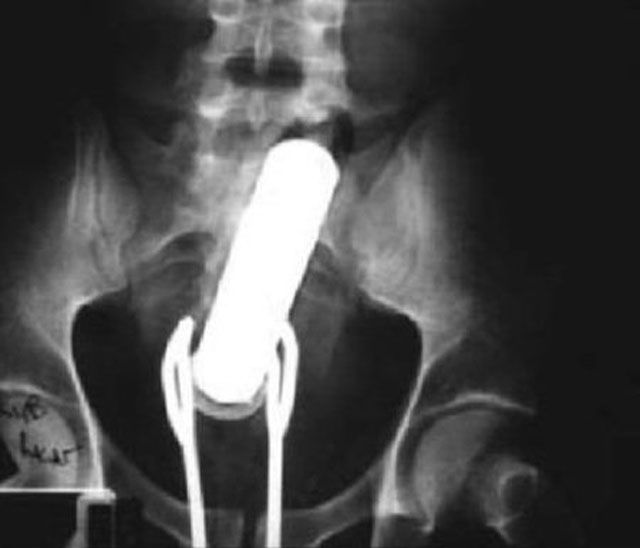

And the old classic: Pint Glass Up The Butt!

This X-ray reveals a cell phone lodged in a Salvadoran prisoner's lower intestine. The man is one of four prisoners who are members of the Mara Salvatrucha street gang. The men were caught with cell phones, spare chips and a charger that they had attempted to smuggle, according to authorities at San Salvador's Zacatecoluca prison.

This X-ray was taken of a 60-year-old man who checked himself into Nishtar Hospital in Multan, Pakistan. He sought treatment because he claimed thieves had inserted a Pepsi bottle into his anus before stealing two of his buffalo.

Getting a vibrator stuck in his bum wasn't enough to send this man to the ER. He simply attempted to remove the stuck object by using a pair of salad tongs. Trouble is, then the tongs got stuck, too!

This incident was not an accident, it was intentional. The late Ryan Dunn of the television show Jackass intentionally inserted a Matchbox car into his rectum just to mess with the ER doctors.